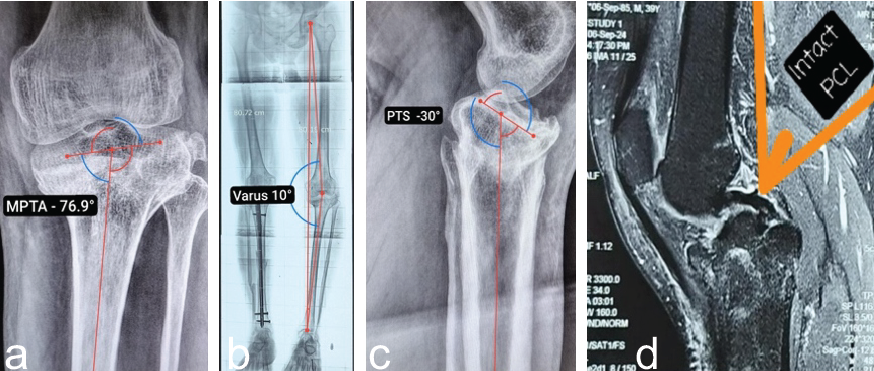

Radiographic evaluation

- Anteroposterior (AP) view: Varus deformity measuring 10°, with a medial proximal tibial angle (MPTA) of 76.9° (Fig. 2a and b).

- Lateral view: Posterior tibial slope reduced to −30°, indicating significant loss of normal posterior inclination (Fig. 2c).

- Computed tomography (CT): Confirmed the decreased posterior tibial slope and provided detailed assessment for surgical planning.

- Magnetic resonance imaging: Confirmed the integrity of PCL (Fig. 2d).

Figure 2: X-rays of left knee. (a) Anteroposterior view demonstrating MPTA 76.9° and (b) scanogram-varus 10°. (c) Lateral View: posterior (reverse) tibial slope −30°. The posterior tibial slope was quantified relative to the anatomic axis of the tibia, established by connecting mid-diaphyseal reference points located approximately 5 cm and 15 cm distal to the tibial plateau, each defined at the midpoint between the anterior and posterior cortical borders on the sagittal plane, and (d) magnetic resonance imaging showing intact PCL.